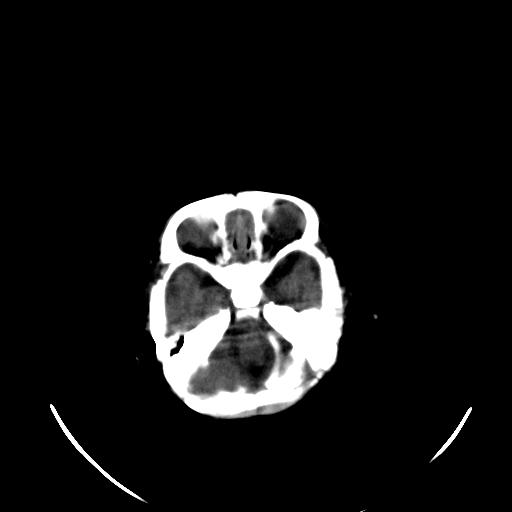

患儿 女性 1个月  今天发现阵发性抽搐  双眼上翻、凝视,嘴唇及面色青紫

考虑双侧脉络膜裂囊肿。

双侧颞枕叶片状低密度影,考虑新生儿却血缺氧性脑病可能

新生儿却血缺氧性脑病不排除!

考虑hie。

考虑新生儿hie。